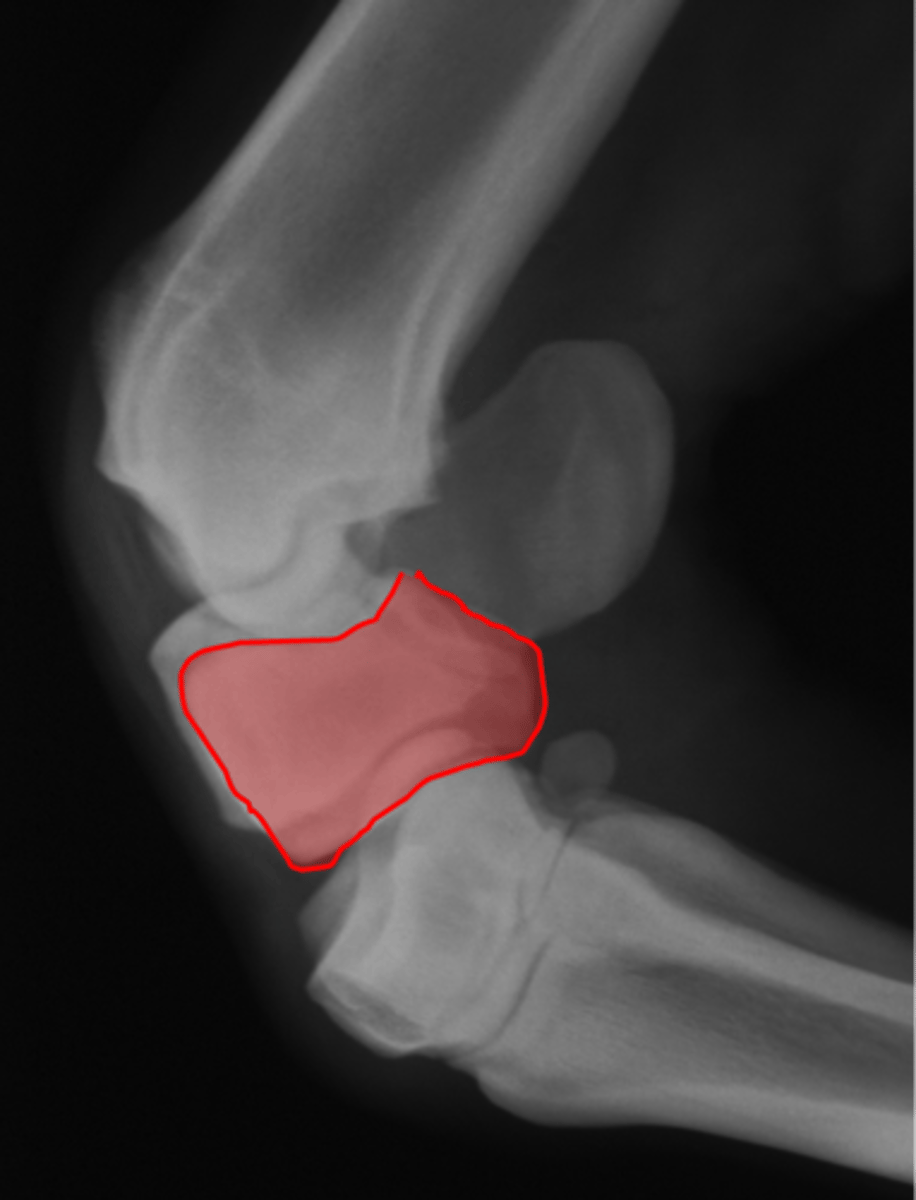

Coffin bone (P3)

Palmar process of P3

Extensor process of P3

DDF

What attaches here?

Navicular bone

Coffin joint

Proximal interphalageal joint (pastern joint)

Short pastern (P2)

Upright pedal or high coronary

What view is this?

Coffin bone

Navicular bone

Pastern joint, LM

ID joint and view

Pastern joint, DP

ID joint and view

Short pastern (P2)

Long pastern (P1)

Pastern joint (proximal interphalangeal joint)